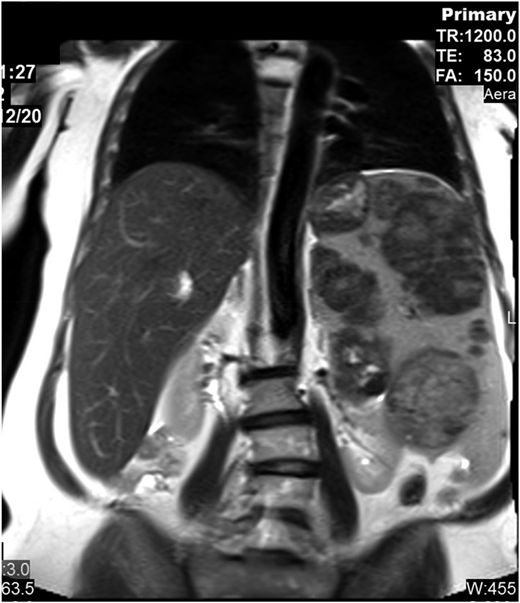

The patient presented at our Gaucher unit in 1998 at the age of 43 years and was married with 6 children. She was referred by the preoperative screening clinic (before repair of an umbilical hernia), where she was noted to have marked hepatosplenomegaly, pancytopenia, and abdominal ultrasonographic findings of multiple splenic lesions, suspicious for malignancy (Figure 2).

Abdominal magnetic resonance imaging showing hepatosplenomegaly with prominent intrasplenic lesions.

Although recognized for almost 140 years, the natural history of untreated GD has not been fully appreciated. Many mildly affected and even asymptomatic patients receive lifelong ERT because their physicians erroneously assume that, without therapy, the disease will invariably deteriorate. However, GD progression (even in those with moderate to severe phenotypes) occurs during childhood, adolescence, and early adulthood with a tendency to stabilize later in life. In the majority of the mild or asymptomatic patients, GD remains unchanged for decades.3 Our moderately affected patient has remained stable for more than 2 decades. Intrasplenic (and less commonly intrahepatic) lesions—hypoechogenic, hyperechogenic, or mixed—are typical in GD, but for the inexperienced radiologist, they may mimic hematological malignancies, as in our patient.4

Two observations are relevant to her clinical course in the era of choices.11 First, patients with GD often maintain stability even when they experience significant disease manifestations, whether they are untreated or nonresponders. Therefore, “maintaining stability” should not be considered a positive endpoint in future clinical trials.12 Second, massive focal lesions within an enlarged spleen predict a poor platelet and splenic response to ERT13 and probably to any specific therapy. Thus, these findings may represent a rare indication for splenectomy even nowadays, which can be performed by hand-assisted laparoscopy even for huge spleens.14